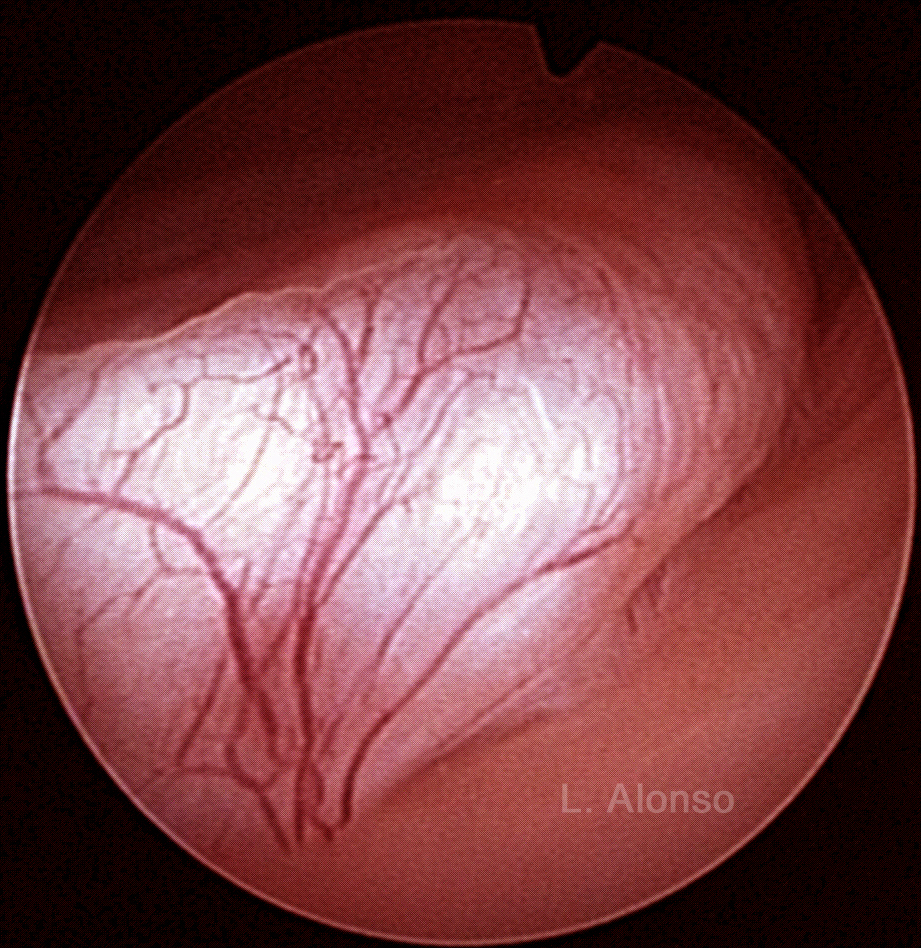

Endometrial polyps originate as focal hyperplasia of the basalis layer of the endometrium and become localized growths of endometrial tissue covered by epithelium containing therein a variable number of glands, stroma and blood vessels. They are usually benign, but 0.5-1% can become malignant.